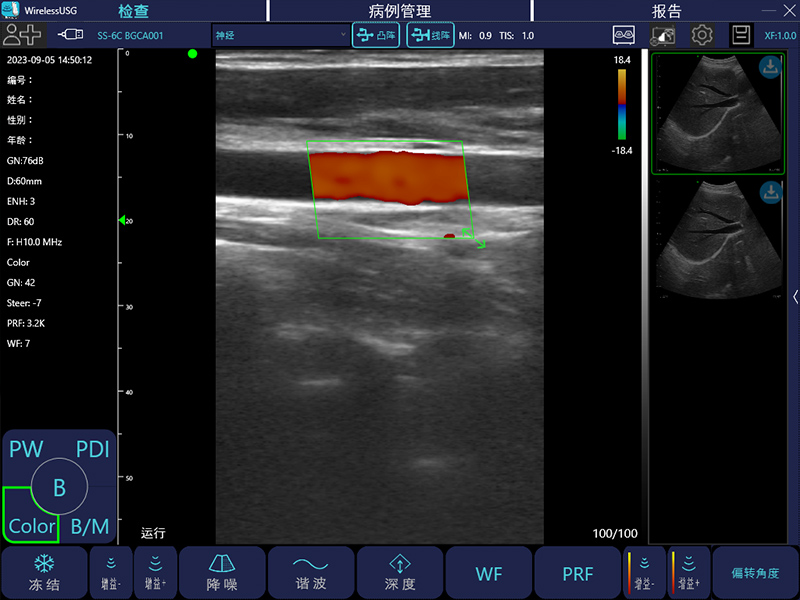

- 成像模式: B、B/M、Color、PW、PDI

- 探头类型:凸阵、线阵、相控阵、微凸、腔内、直肠

线阵:7.5MHz/10MHz,20/40/60/100mm,40mm

- 图像调节:黑白图像增益、分段增益TGC、动态范围、焦点、深度、反相脉冲谐波、降噪、彩色增益、血流采样框大小、PRF